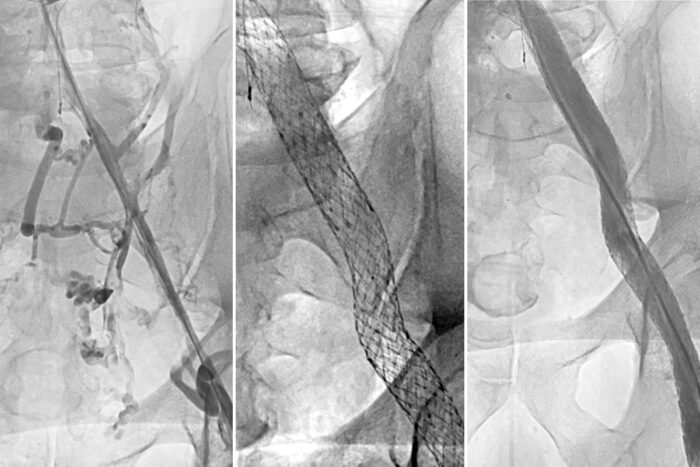

Radiographic images of veinsCourtesy Suresh Vedantham

The study enrolled 225 patients at 29 sites across the U.S. who had been treated for deep vein thrombosis for at least 3 months and had blockage of the iliac vein (a major vein in the pelvis) causing substantial disability. Patients were chosen at random to receive either a stent — a mesh tube inserted into the vein to reinforce and expand it — plus standard treatment with compression and blood-thinning medications, or standard treatment alone. A stent is placed in a two-to-three-hour operation that requires only tiny incisions.

At the start of the study, 93% of participants met the clinical criteria for severe post-thrombotic syndrome. Six months after treatment, just 40% of patients who received the stent still experienced severe post-thrombotic syndrome, compared to 61% in the standard care group.